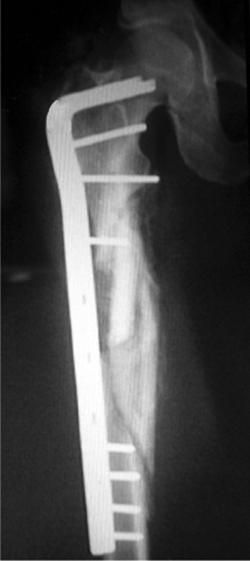

![]() |

Figure 19.16. Anatomic alignment and healing of a comminuted subtrochanteric fracture.